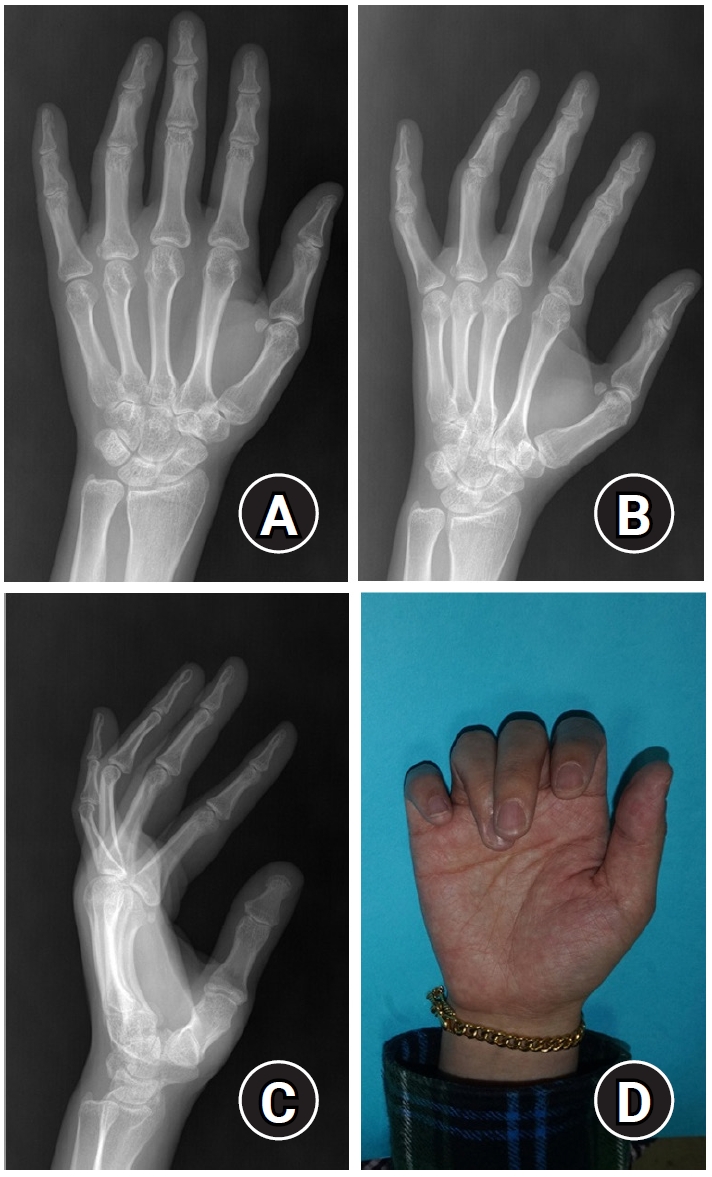

In the case of extraarticular transverse fractures of the proximal phalanx, even if the fracture does not appear severe on X-ray alone, rotational deformity may still be present. Therefore, a diagnosis should not be based solely on X-ray findings, and a thorough physical examination should be performed before surgery to prevent the complication of rotational malunion [9] (Fig. 3).

Proximal phalanx fracture of fourth finger with difference between X-ray findings and physical examination. Fracture of the proximal phalanx base of the fourth finger was shown with minimal displacement on the X-ray (A-C). However, finger overlap due to rotational displacement was observed on physical examination (D).